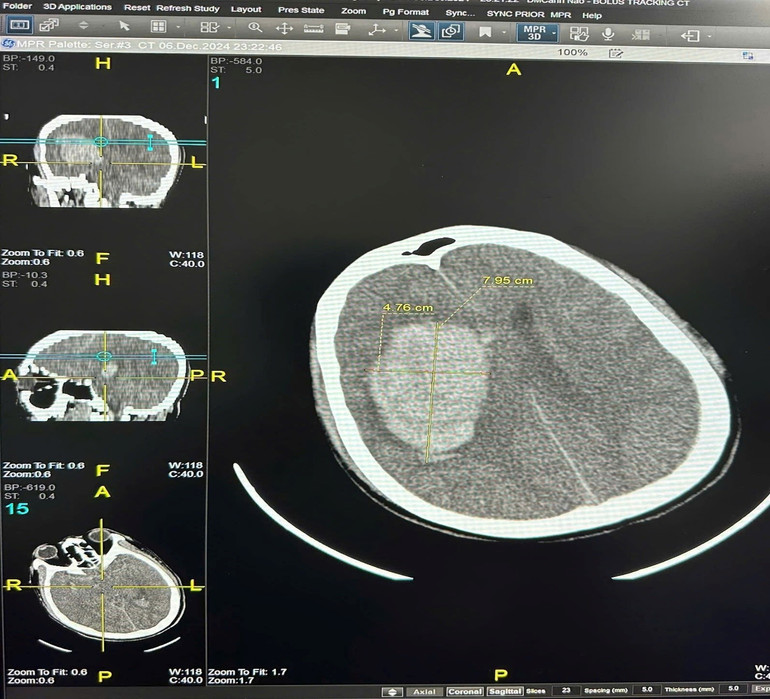

Đêm ngày 6/12, khi bắt đầu đợt không khí lạnh gần đây nhất, bệnh nhân Đ. phải nhập viện cấp cứu trong tình trạng hôn mê sau khi tắm khuya. Kết quả chẩn đoán cho thấy xuất huyết não với khối máu 90cm³, và bệnh nhân buộc phải phẫu thuật mở sọ để giải ép áp lực não, hiện tại bệnh nhân vẫn phải điều trị tích cực, duy trì thở máy, tiên lượng rất nặng.

| Hình ảnh phim CLVT của bệnh nhân Đ.V. Đ: khối máu tụ bán cầu phải với thể tích khoảng 90cm3. |